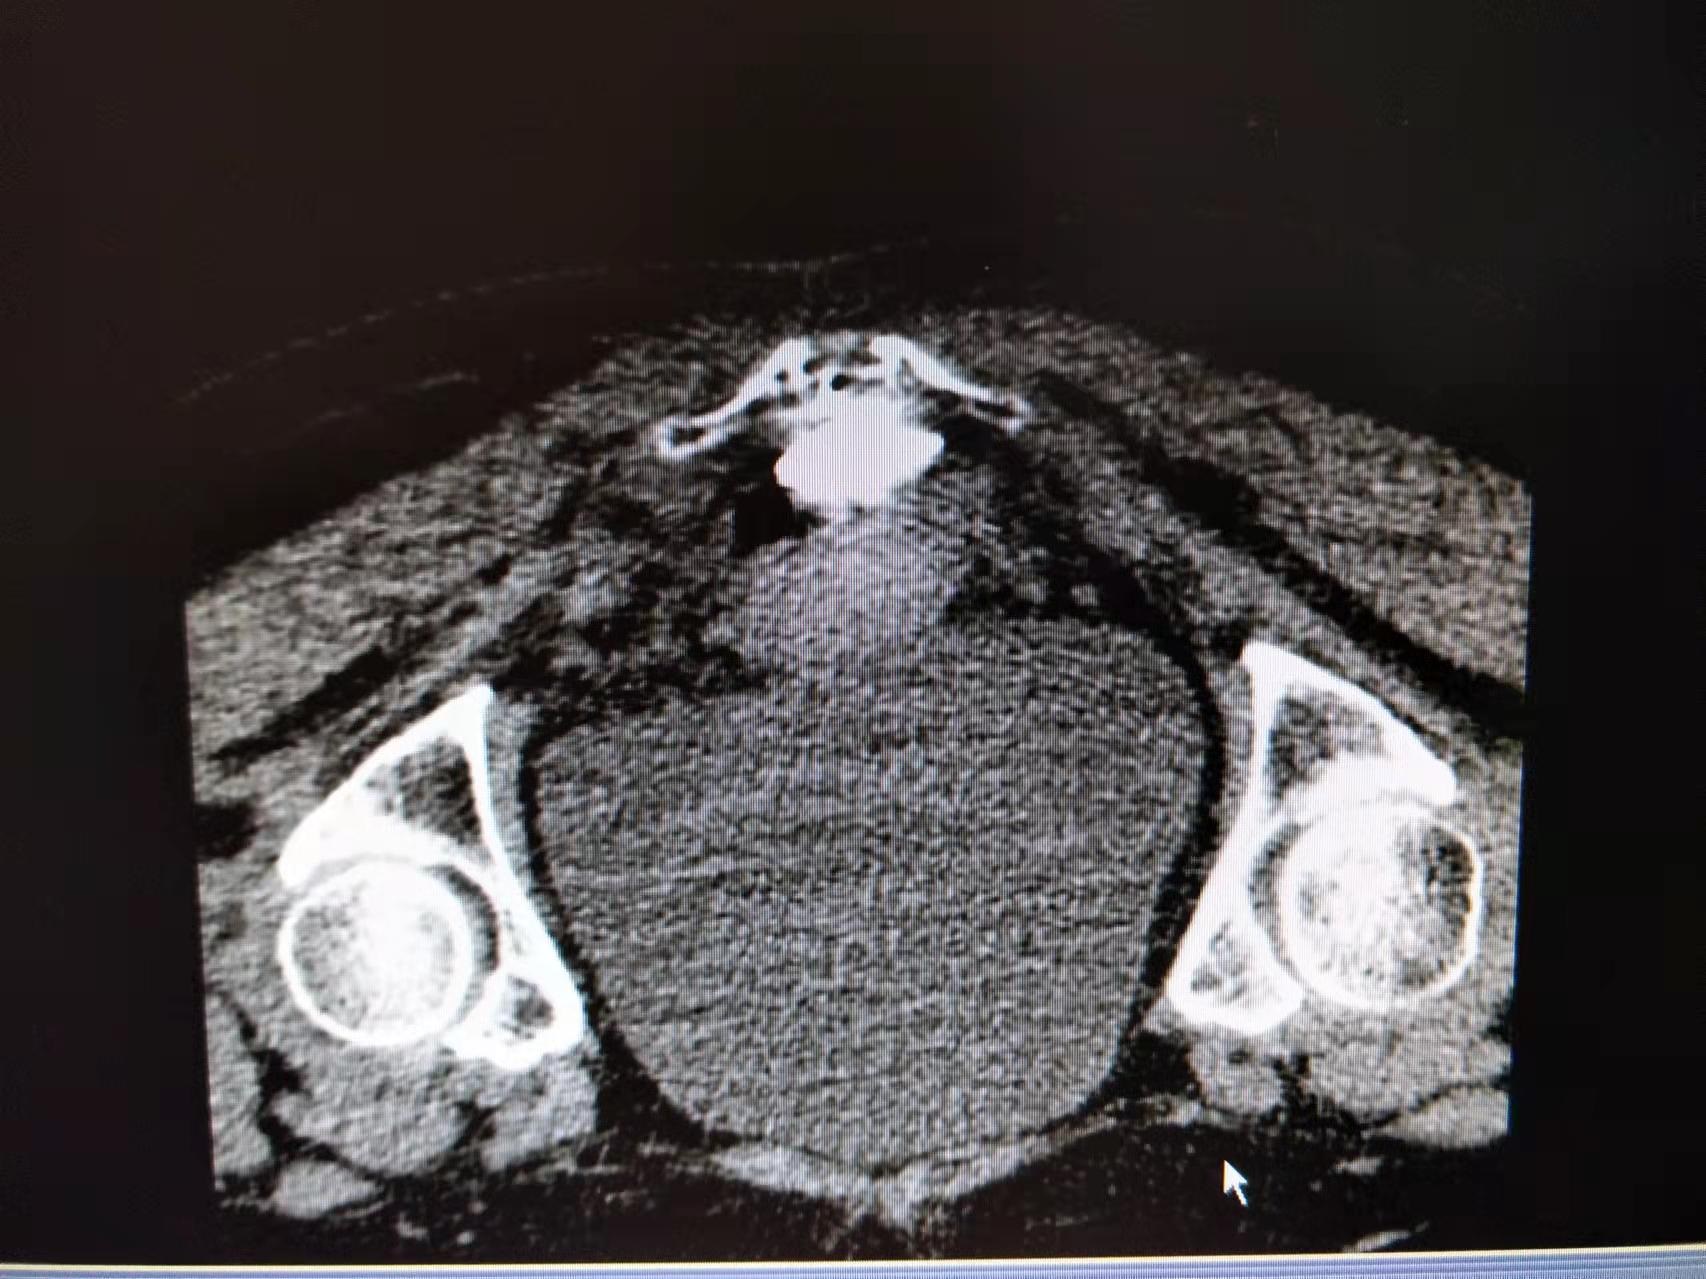

顽固性会阴痛难以启齿却困扰着很多病友,这是一例CT引导下精准化奇神经毁损治疗顽固性会阴痛,治疗后第二日便收获了病友大大的赞。